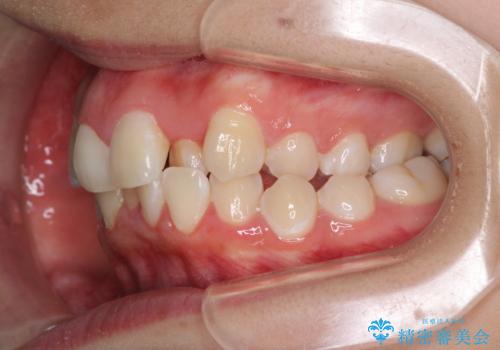

- 骨格的な咬み合わせのズレ、前歯のデコボコとクロスバイトを気にして来院された患者様です。

口元の突出感が若干あり口が閉じにくく、デコボコが強いため、上下左右の小臼歯計4歯を抜歯し、ワイヤー装置による矯正治療を行うこととしました。

また、舌の突出癖が強く、下顎前歯が前方に押し広げられる可能性が高いため、舌癖の改善を継続的に行うよう指示しました。